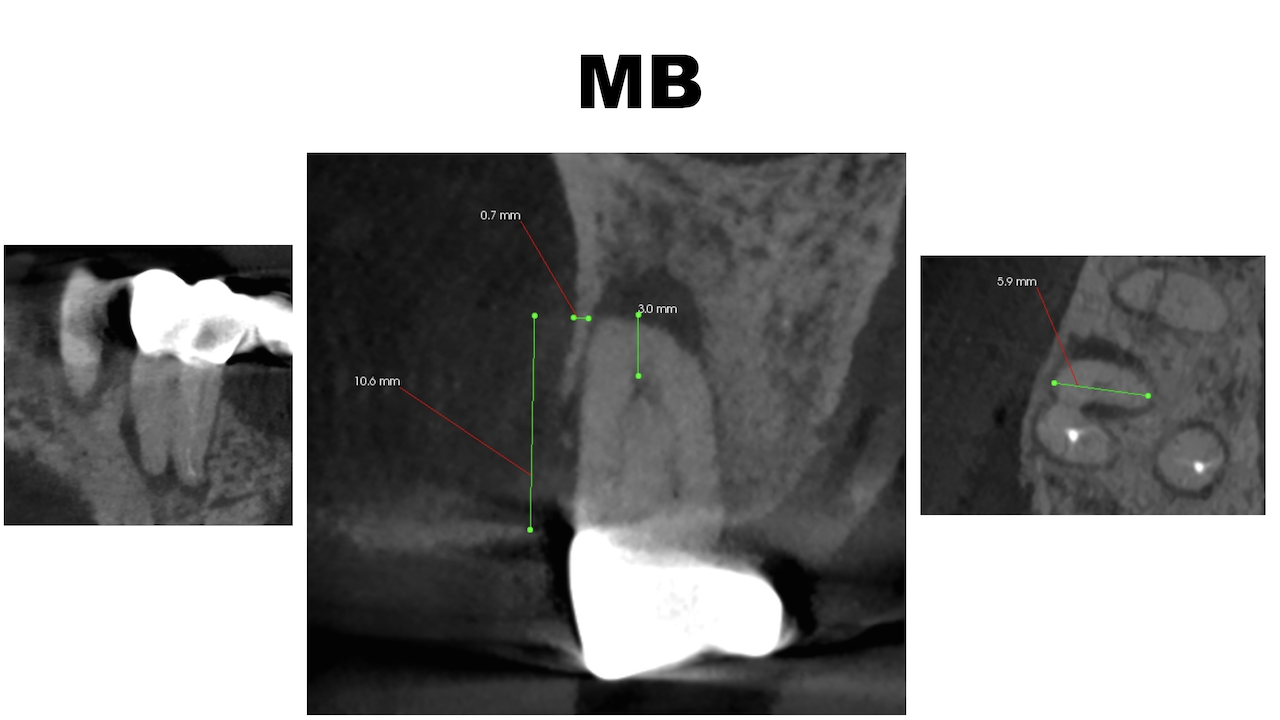

Pre-op CBCT(2024.11.25)

MB

P根以外のMB,DBには根尖病変がありSinus tractがある。

ということは…

MB+DB Apicoectomyだ。